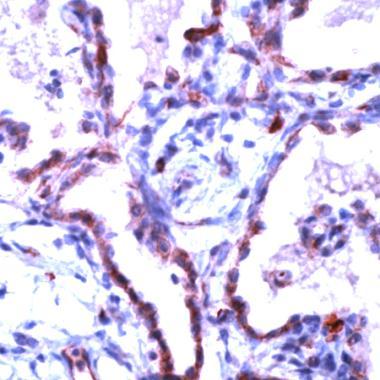

- Human Lung stained with anti-Claudin-5 antibody (GTX15106)